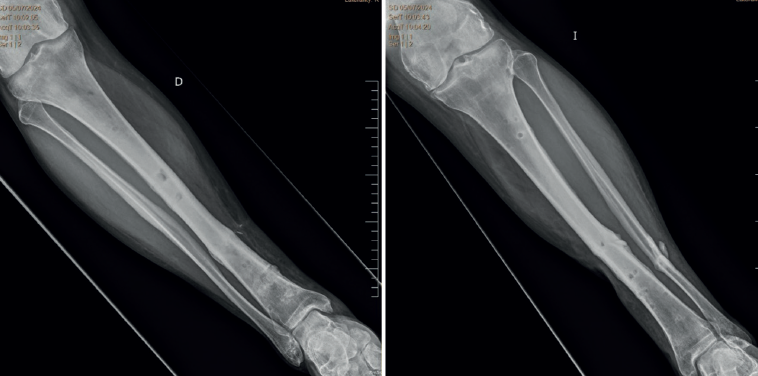

Ante la buena reducción y corrección de la fractura, 7 meses después se decide su ingreso y realizar cirugía programada de retirada del TSF de la tibia derecha, sin incidencias en el ingreso. El mes siguiente se realiza la retirada del TSF de la tibia izquierda.

Al año de la retirada de los TSF la fractura está completamente consolidada (Figura 4).

Clínicamente, el paciente no tiene dolor y camina sin apoyo externo. A la exploración de ambas piernas se encuentran las heridas de los pines cicatrizadas, sin supuración, leve déficit de flexión dorsal del primer dedo del pie izquierdo y movilidad articular disminuida en últimos grados de flexión dorsal y plantar en ambos tobillos.